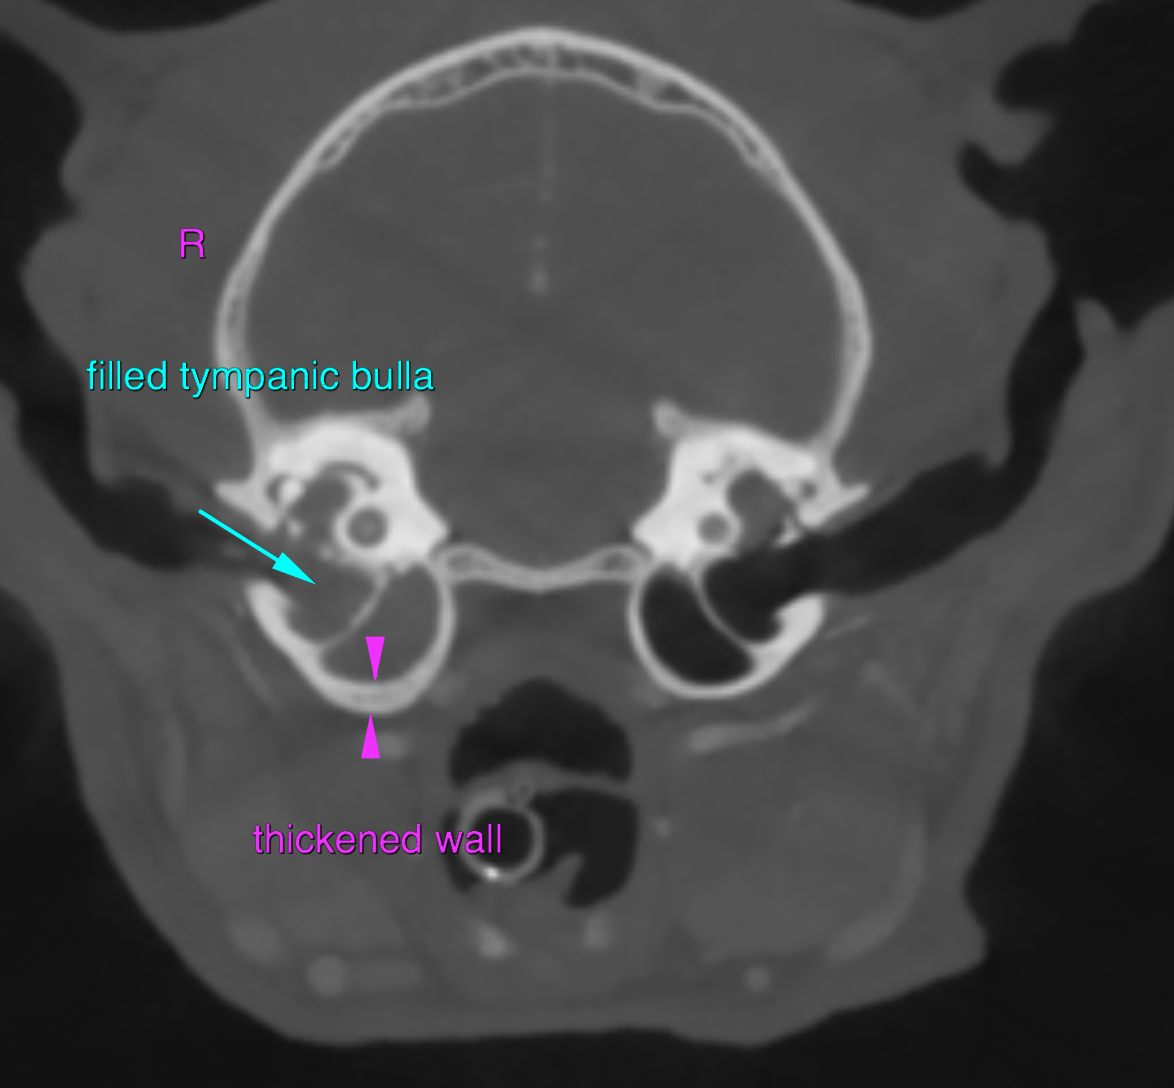

The right tympanic bulla presents a moderately thickened but smooth wall and contains uniform soft tissue attenuating and peripheral contrast enhancing material. In comparison to the contralateral side, the diameter of the osseous part of the auditory tube is moderately increased. A uniform soft tissue attenuating and peripheral contrast enhancing space occupying lesion is protruding from the right dorsolateral aspect of the nasopharynx – level with the opening of the auditory tube – into the lumen of the nasopharynx, occupying approximately 95% of its cross-sectional area.

Right sided chronic otitis media

Nasopharyngeal soft tissue mass, originating from the right tympanic bulla, causing upper airway obstruction

Secondary pressure induced mild atrophy of the osseous part of the right auditory tube

The findings are consistent with chronic inflammatory nasopharyngeal polyp originating from the right tympanic bulla.